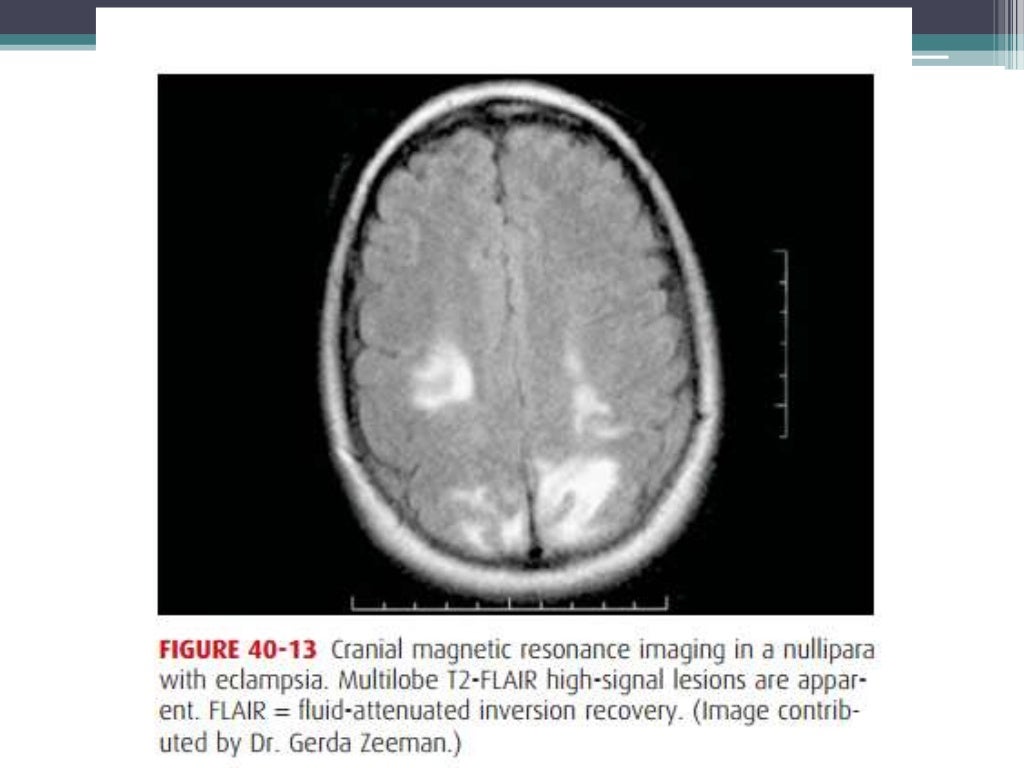

Prognosis and complications of eclampsia Eclampsia Prognosis however, some studies suggest that pres might be indicative of a more severe disease process. rates of preeclampsia have steadily increased over the past 30 yr, affecting ∼4% of pregnancies in the. this topic will discuss the intrapartum and postpartum management of pregnancies complicated by. despite advances in detection and management, preeclampsia/eclampsia remains a common cause. Eclampsia Prognosis.